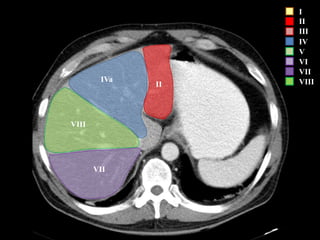

COUINAUD asignó un sistema de numeración para definir la segmentación

hepática.

I

II

III

IV

V

VI

VII

VIII

IVa

I – Entre cava y porta

II – el más superior de los izquierdos

III – Por debajo del II

IV – por delante de la vesícula

V – por detrás de la vesícula

VI – relación con riñón derecho

VII – el más posterior de los segmentos superiores

VIII – domo hepático

Las claves de la segm. Hepática